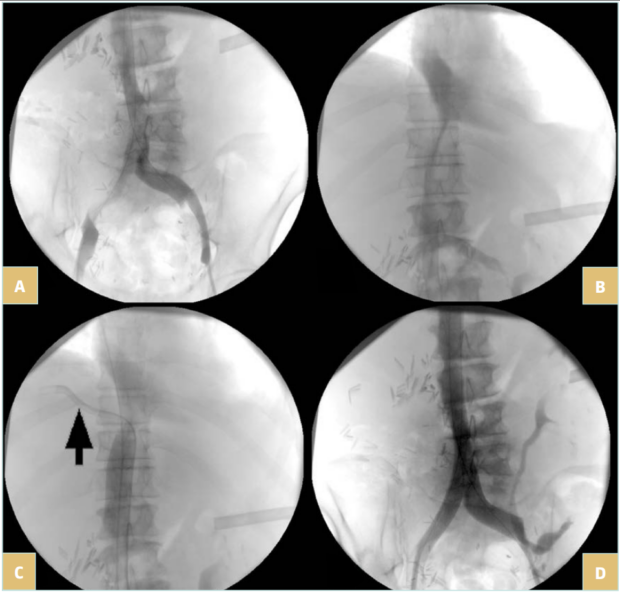

Once the lesion is crossed (Figure 4A and 4B), super stiff or extra stiff guidewire and then a larger sheath are inserted (10-12 Fr depending on balloon and stent needs) and intravenous heparin should be given at the dose of 50 UI/kg. At this time, IVUS can be used to ensure a better evaluation of the lesion.6 Pressure gradient measurements can be performed but have value only if positive (the absence of pressure gradient can be due to collateral pathways, even more in a patient that is lying down). Then predilatation is performed using high-pressure balloons of progressive diameter mainly in case of postradiotherapy lesions (in these cases, downsizing by 2 mm in diameter compared with a standard procedure is recommended to avoid venous rupture).

Stenting is then performed using self-expanding stents (Figure 4C and 4D). Different stents were used in the literature. Until 2010, Wallstent (Boston Scientific, Marlborough, Massachussetts, USA) and Gianturco Z stent (Cook Medical, Bloomington, Indiana, USA) were the 2 most used stents. Since the development of nitinol self-expanding stents, many others have become available, though some of them are designed for femoro-iliac veins (Venovo, Abre). Stent sizing depends not only on the diameter of the adjacent nonpathologic IVC size—that can be evaluated by CT scan or IVUS—but also to the tumor. In most cases 18 to 22 mm in diameter should be used for the IVC as larger stents can have difficulties with expanding; too-small stents can migrate and also limit flow. Few nitinol stents are available in 20-mm diameter or higher (see Table I). These stents have a more precise deployment than the Wallstent without foreshortening. Regarding stent length, they should cover at least 15 to 20 mm beyond the obstructive lesion at both ends, covering an area that goes not only from healthy-to-healthy segment but also includes a safety margin to avoid restenosis by tumor progression.9,10 When multiple stents are needed, an overlap of at least 20 mm should be used. In case of biiliocaval lesions, different stent configurations can be used: the Eiffel tower configuration while deploying the IVC stent first, then both iliac stents simultaneously (Figure 4D), or a double-barrel technique (mostly if lesions are limited to the iliocaval confluence).

Figure 4. 76-year-old man suffering from right iliac and inferior vena cava (IVC) compression by iliac and infrarenal IVC nodes and liver metastasis from urothelial cancer with ascites (history of cystectomy and right uretero-nephrectomy): A) compression of the right iliac vein and infrarenal IVC; B) compression of the suprarenal IVC; C) after angioplasty and stenting of the suprarenal IVC; a guidewire (arrow) was positioned in the suprahepatic vein before stent deployment; D) after

biiliocaval stenting according to the Eiffel tower technique.